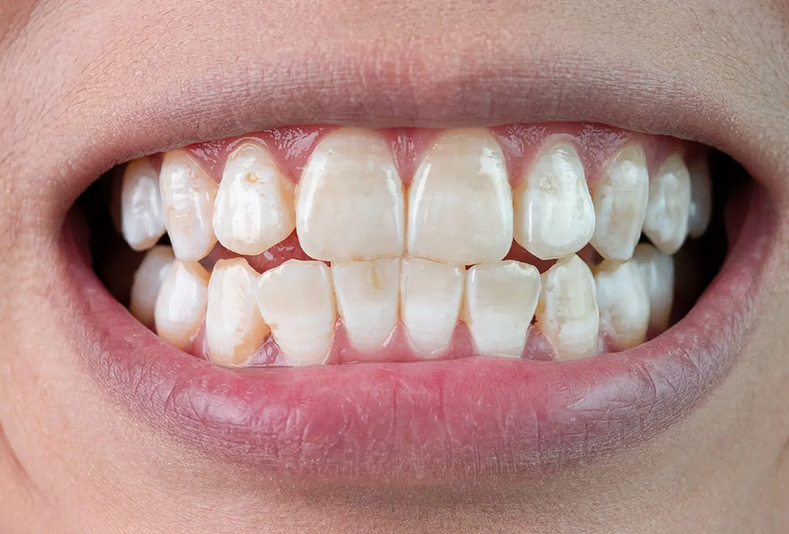

Discromie dentali tecniche di intervento

Igiene dentale

Tecniche di intervento e gestione clinica delle discromie dentali

08 Settembre 2025